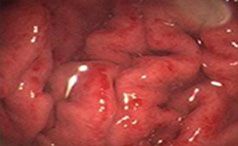

结肠炎是指结肠黏膜的炎症性疾病,根据病程可分为急性和慢性两类。该病在全球范围内的发病率呈上升趋势,已成为消化系统常见疾病之一。...【详情】

常见症状:腹痛、腹泻、便秘

左下腹或小腹部出现隐痛或绞痛

【导语】慢性结肠炎是临床常见病、多发病,常易反复发作,一般很难治愈,......【详情】